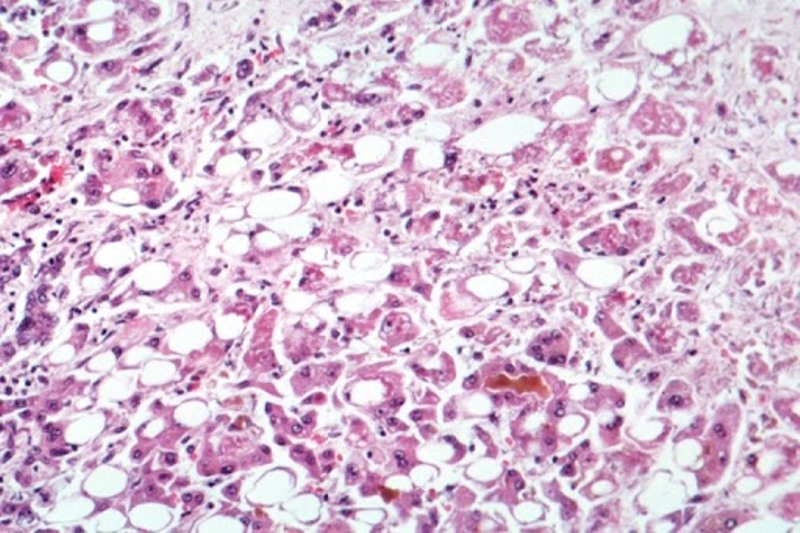

Toronto/IBNS: Cases of severe liver disease "of unknown origin" among children in Canada are being investigated by public health officials as a mysterious hepatitis outbreak has reportedly affected nearly 200 youths around the world.

According to the latest available data from the World Health Organization (WHO), at least 169 cases of acute hepatitis of unknown origin have been reported in close to a dozen countries, with 114 from the United Kingdom.